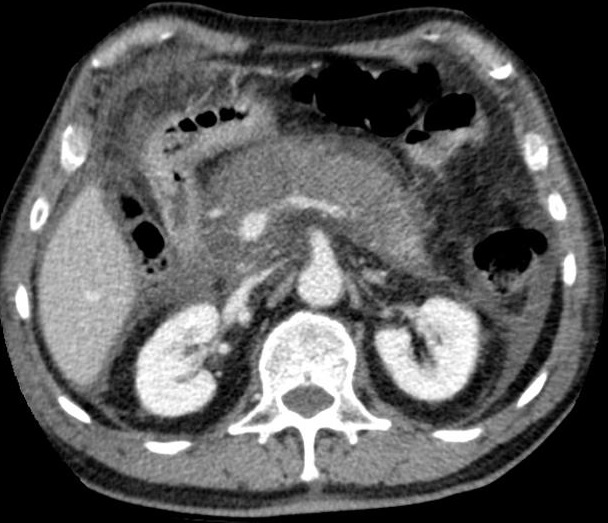

Image radiologique TDM de pancreatite oedemmateuse

benigne sont : Au stade de debut image radiologique peut

etre normale ou en volumineuse . Au stade avance le pancreas

est volumineuse, en siegant des oedeme hypodensite

localise ou diffuse dans la parenchyme dupancreas , ce

qui entraine une perte de sa lobulation physiologique , sa

contour devient flou et le diametre antero-posterieure de la

tete du pancreas depasse diametre tranvesale du corps

vertebrale ajacent . Oedeme peut en depasse au dela du

pancreas ce qui done de image de densification de la graisse

peri -pancreatique et epaissisement de fascia para

renale

Aspect

radiologique TDM une pancreatite aigue form

oedemateuse : epaissisement du diametre antero

posterieure avec epanchement legere parapancreatique

. Image radiologique TDM C+ phase veineuse , en

coupe axiale . |